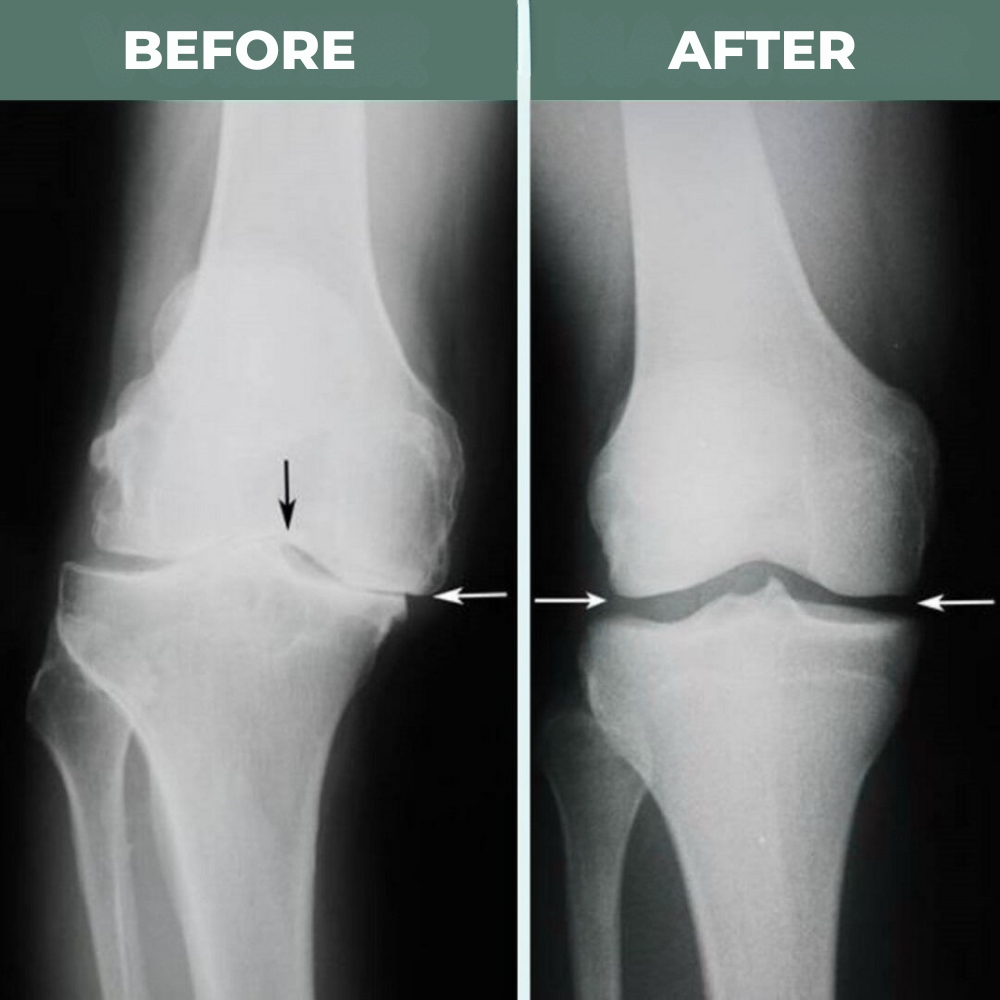

Age, previous injuries, or years of wear and tear can cause the kneecap to slip out of its natural track. Body weight is then no longer evenly distributed in the joint.

The result? Some areas are subjected to excessive strain, while others barely function properly. This leads to constant irritation, friction, and those persistent pains that you feel day after day.

Over time, this uneven stress wears down the cartilage, destroys the protective padding in the knee, and eventually develops into osteoarthritis.